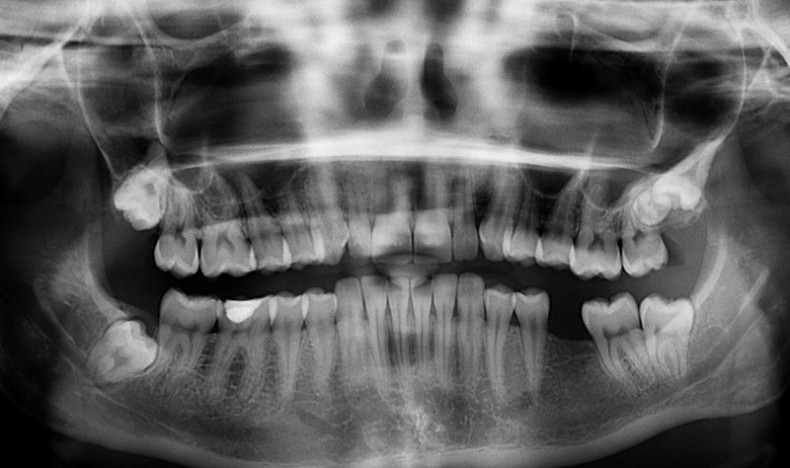

Inflammatorisk tarmsykdom som ulcerøs kolitt (UC) og Morbus Crohn (MC) kan påvirke tannhelsen din betraktelig, skriver IBDrelief.com.

Et studie gjort på svenske pasienter diagnostisert med inflammatorisk tarmsykdom (IBD) som UC og MC trenger mer tannbehandling enn kontrollgruppen, og behøver flere kariesrelaterte behandlinger.

Forskjellen fra kontrollgruppen var størst når det gjelder behov for rekonstruerende tannbehandling hos Crohnspasienter.

IBD-pasienter har altså større sjanse for å få hull i tennene og infeksjoner i munnen og trenger mer behandling hos tannlegen enn hos folk uten IBD.